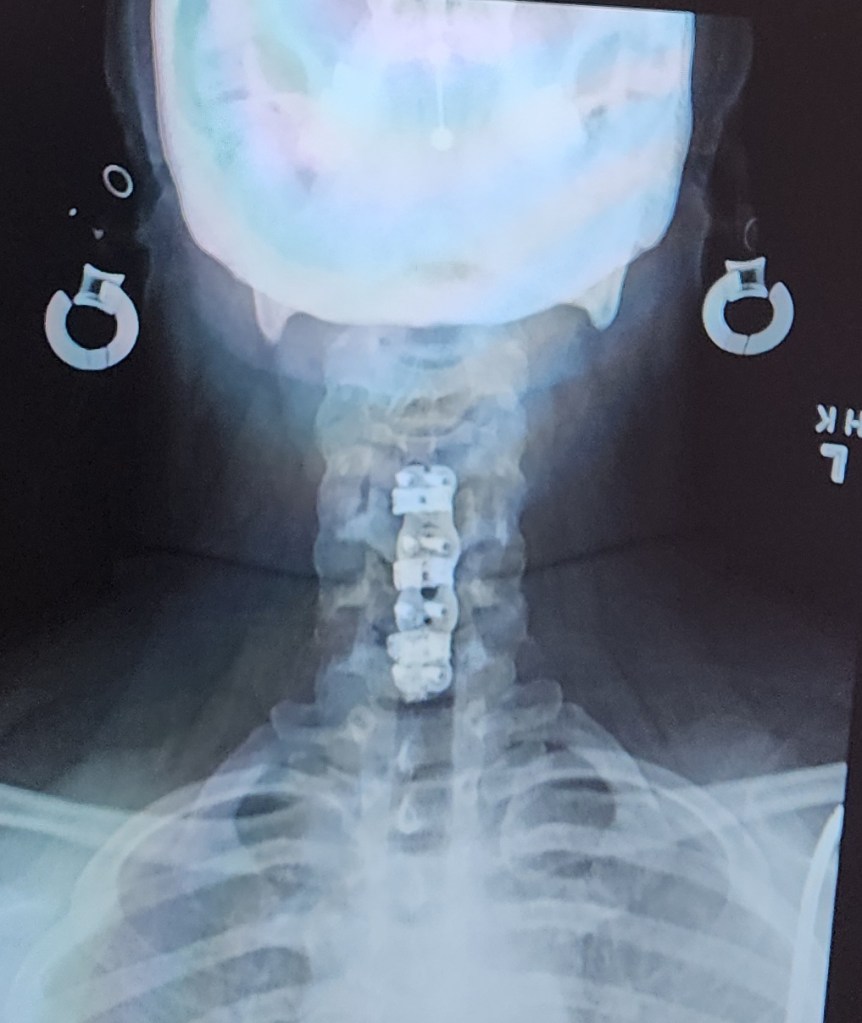

Artemis died at the end of August 2024, 3 days before I was to have surgery to remove 3 disks from my neck. His health declined quickly, and had to be taken to the vet to be put to sleep due to heart failure. Apparently it was a long time coming, and the vet was surprised he didn’t pass sooner. Phoenix and Artemis loved each other. They often slept curled up together. Months after Artemis died, if his name was said, Phoenix would look around the house for him. If there is life after death, I know that they are together again.